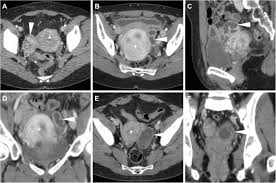

Malignancy: Cancer can spread to the abdomen and cause fluid buildup in the cul-de-sac.

Fluid buildup in the cul-de-sac can cause a variety of symptoms, including pelvic pain, abdominal pain, and fever. It can also be a sign of a more serious underlying condition.

Why is trace ascites in the acute setting important? While trace ascites is often harmless, it can sometimes be a clue to a serious medical issue, like appendicitis, a ruptured appendix, or a bowel obstruction. These conditions require immediate medical attention.

What should you do if you have trace ascites? If you experience sudden abdominal pain, especially if accompanied by a trace of fluid, seek medical advice immediately. Your doctor will perform a thorough examination and run tests to determine the cause of your symptoms.